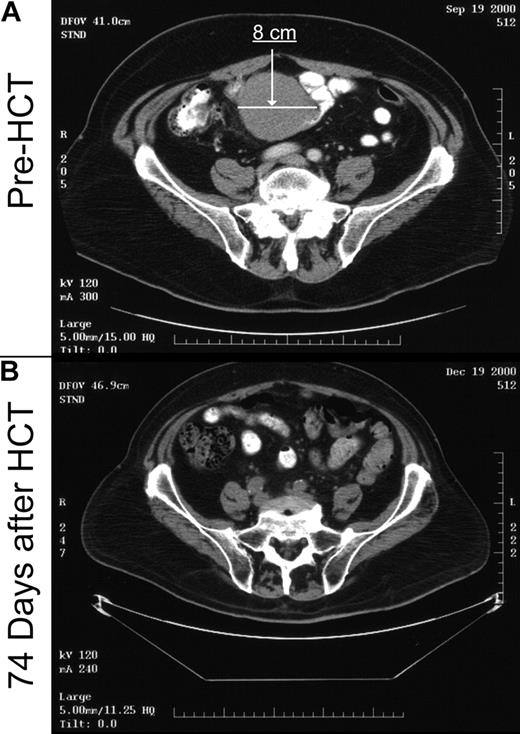

At the time of HCT, 19 patients had measurable disease by CT scan, and one patient had evidence for disease by flow cytometry (Table 3). The disease response rate after transplantation was 85%. An example of an antitumor response after an unrelated donor nonmyeloablative HCT in a heavily pretreated patient with bulky disease who had failed autologous HCT is shown in Figure 2. CR was achieved by 15 patients (75%), including the one with flow cytometry evidence of disease, PR was achieved by 2 patients (10%), and 3 patients (15%) experienced disease progression. The median time to CR was 87 days (range, 21 to 244 days). One of the 15 patients who achieved CR had disease relapse 5 months after HCT, whereas the others have remained in CR. In the time-dependent analysis of the relationship of disease response with GVHD, there was no association between disease response and grades I to IV acute GVHD (P = .36), but a trend was observed with chronic extensive GVHD (P = .09). With an observation time of 24.6 months, all 13 patients who underwent transplantation without evidence of disease have remained in CR. In the patients with progressive disease, one refused further direction or follow-up from the transplant center, one could not have immunosuppression discontinued due to GVHD and concurrent aspergillus infection, and the other 2 had fulminate early lymphoma progression unresponsive to immunosuppression discontinuation. The Kaplan-Meier probability of overall progression-free survival was 60% (95% confidence interval: 43%-78%) at 2 years, and corresponding figures for recipients of related and unrelated grafts were 56% and 66%, respectively (Figure 3). The cumulative probability of relapse at 2 years was 16%. In univariate analysis, the only pretransplantation factor predictive of relapse was the number of preceding treatment regimens. None of 14 patients with less than 4 treatment regimens experienced relapse, compared with 4 of 19 patients with at least 4 regimens (P = .01).

Figure 2.

Example of graft-versus-tumor response. Patient no. 20, as shown in Table 1, was a 69-year-old man with rapidly progressive mantle cell NHL. Prior treatments included 8 lines of chemotherapy with only a 6-month remission to high-dose radiolabeled antibodies with autologous peripheral blood stem cell support. At the time of transplantation, he had kinetically failed Etoposide, Methylprednisolone, Ara-C Cisplatin (ESHAP), with rapidly progressive disease during the pretransplantation workup. (A) Pretransplantation computed tomography (CT) scan image (day –27) through the upper pelvis demonstrating an 8-cm by 7-cm mass that extended through twelve 0.5-cm cuts. (B) CT scan image through the same region demonstrating complete resolution of the mass on day +74 after nonmyeloablative transplantation from a matched unrelated donor. The patient remains in remission 30 months after transplantation with no evidence of GVHD.